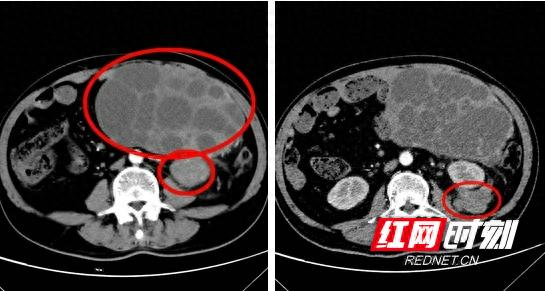

近期,一名女性患者的右侧乳房恶性肿瘤迅速增大,体积已达到篮球大小。这一变化导致她行走困难,肿瘤溃烂,轻轻触摸便会大量出血,并伴有恶臭,严重影响了她的生活质量。此外,她还面临随时可能发生的血崩和休克风险。令人遗憾的是,DIEP手术的难度极大,目前国内能够开展此类手术的医院数量极为有限。

手术的挑战相当严峻。患者病史较长,肿瘤可能已侵犯乳房周围血管,导致血管游离与缝合过程充满挑战。这一状况直接影响到手术的流畅进行和最终成果。对于患者的手术结果,人们普遍感到担忧,手术的复杂程度远超预期。

患者亟需治疗,肿瘤可能随时破裂引发大量出血。这情形宛如一场与时间的竞赛,手术需迅速展开。种种不确定性对手术团队构成了巨大压力。